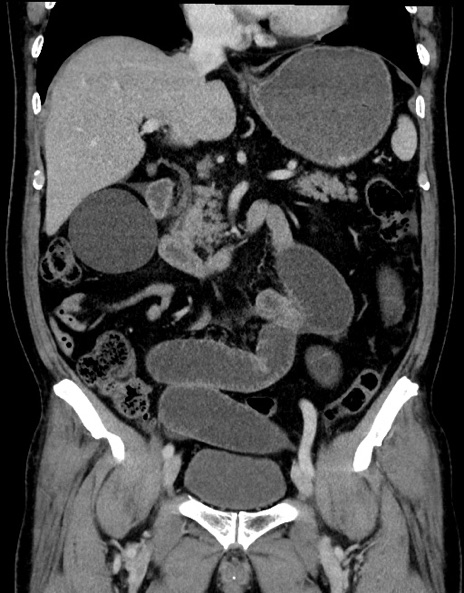

横断像

症例15(冠状断像)

【症例】70歳代男性

【主訴】腹痛

【現病歴】今朝から腹痛あり。全体的に痛い。特に左上の方。排ガスが今日はない。冷や汗が出る。

【既往歴】直腸癌術後

【身体所見】左側腹部〜上腹部に圧痛あり。腹膜刺激症状明らかなではない。軽度反跳痛。左下腹部に術後瘢痕あり。

【データ】WBC 7700、CRP 0.02